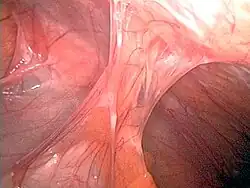

Adhesions formed following appendectomy

Adhesions are fibrous bands that form between tissues and organs,[1] often as a result of irritation of internal surfaces during surgery, infections or trauma. They may be thought of as internal scar tissue that connects tissues not normally connected.